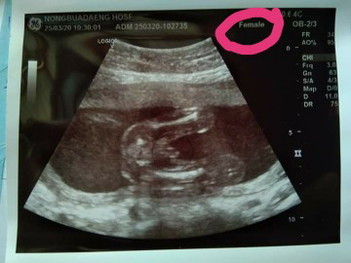

ไปซาวด์เพศมา หมอบอกเป็นเพศชาย ชี้จู๋ลูกให้ดู แล้วทำไมตรงที่วงไว้ เป็นเพศหญิงค่ะ คึงงมากค่ะ

ตรงที่วงกลมคือเพศของแม่ค่ะ 😁

555. ไม่รุ้จิงๆ ขอบคุนจ้าา